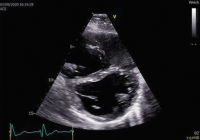

Abbildung 3: Patient mit rechtsventrikulärer Volumsbelastung bei schwerer Trikuspidalinsuffizienz.